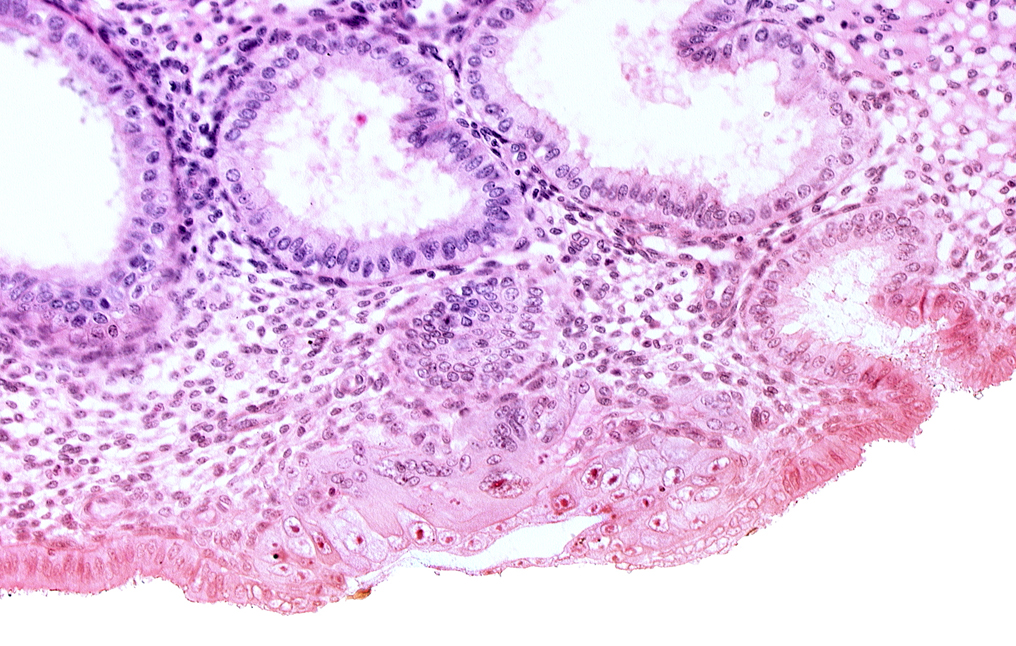

Carnegie Embryo #8020 | Location: 05-06-07

Keywords: blastocystic cavity (blastocoele), cytotrophoblast, endometrial epithelium, endometrial gland, endometrial sinusoid, membranous trophoblast at abembryonic pole, mouth of endometrial gland, uterine cavity

Source: The Virtual Human Embryo.